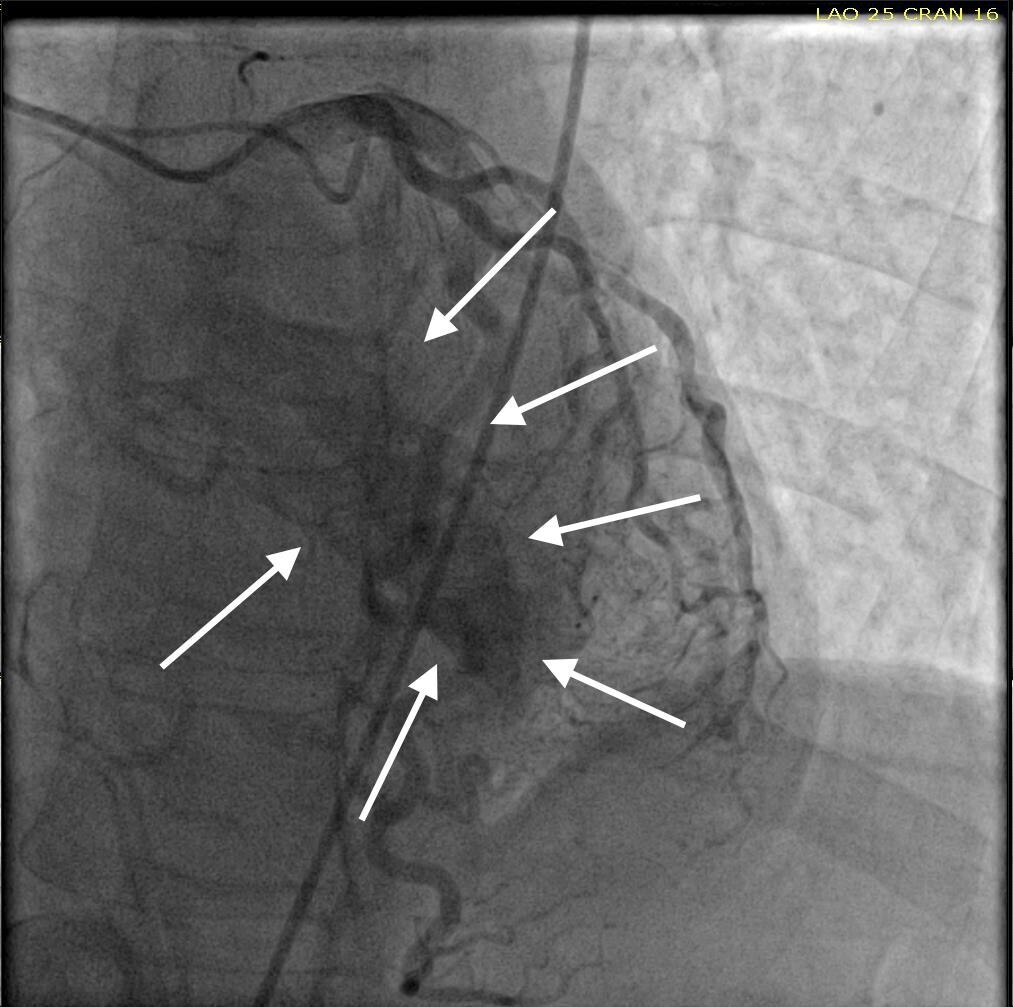

She was taken for a diagnostic left heart catheterization which showed mild to moderate disease in multiple coronary arteries with severe stenosis of a small caliber mid right sided Posterior Descending Artery (rPDA) not amenable to percutaneous intervention. The cardiac catheterization also revealed an extensive network of microfistulae forming communications between all three major coronary arterial branches (i.e., LAD, Right Coronary Artery [RCA], and Left Circumflex [LCx]) and the LV cavity (Figures 2, 3, and 4). This patient’s flow through her microfistulous communications was so brisk that a perfectly interpretable left ventriculogram was visualized with coronary angiographic imaging via a hand injection of contrast into the left coronary arterial system (Figures 3 and 4).

It was not possible to quantitate this patient’s amount of flow through her extensive thebesian venous network since it is generally extremely technically difficult to do so.7 However, it was obvious that this woman’s total thebesian venous flow far exceeded the upper limit of what is considered typical since her LV ejection fraction (normal being in the range of 54 - 74% in women) could easily be interpreted with a hand injection during left coronary artery angiography. On the second day after admission, complete 2D echocardiography was performed only showing moderate LV hypertrophy.